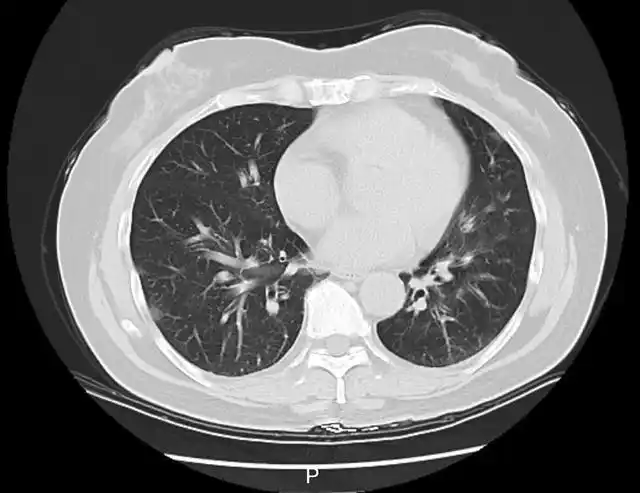

检测结果显示,李阿姨已经得了病毒性肺炎,甲型流感病毒核酸呈阳性。这一下,罪魁祸首找到了,是甲流搞砸了这一家人一次本该圆满的旅行。

图|李阿姨肺部CT影像